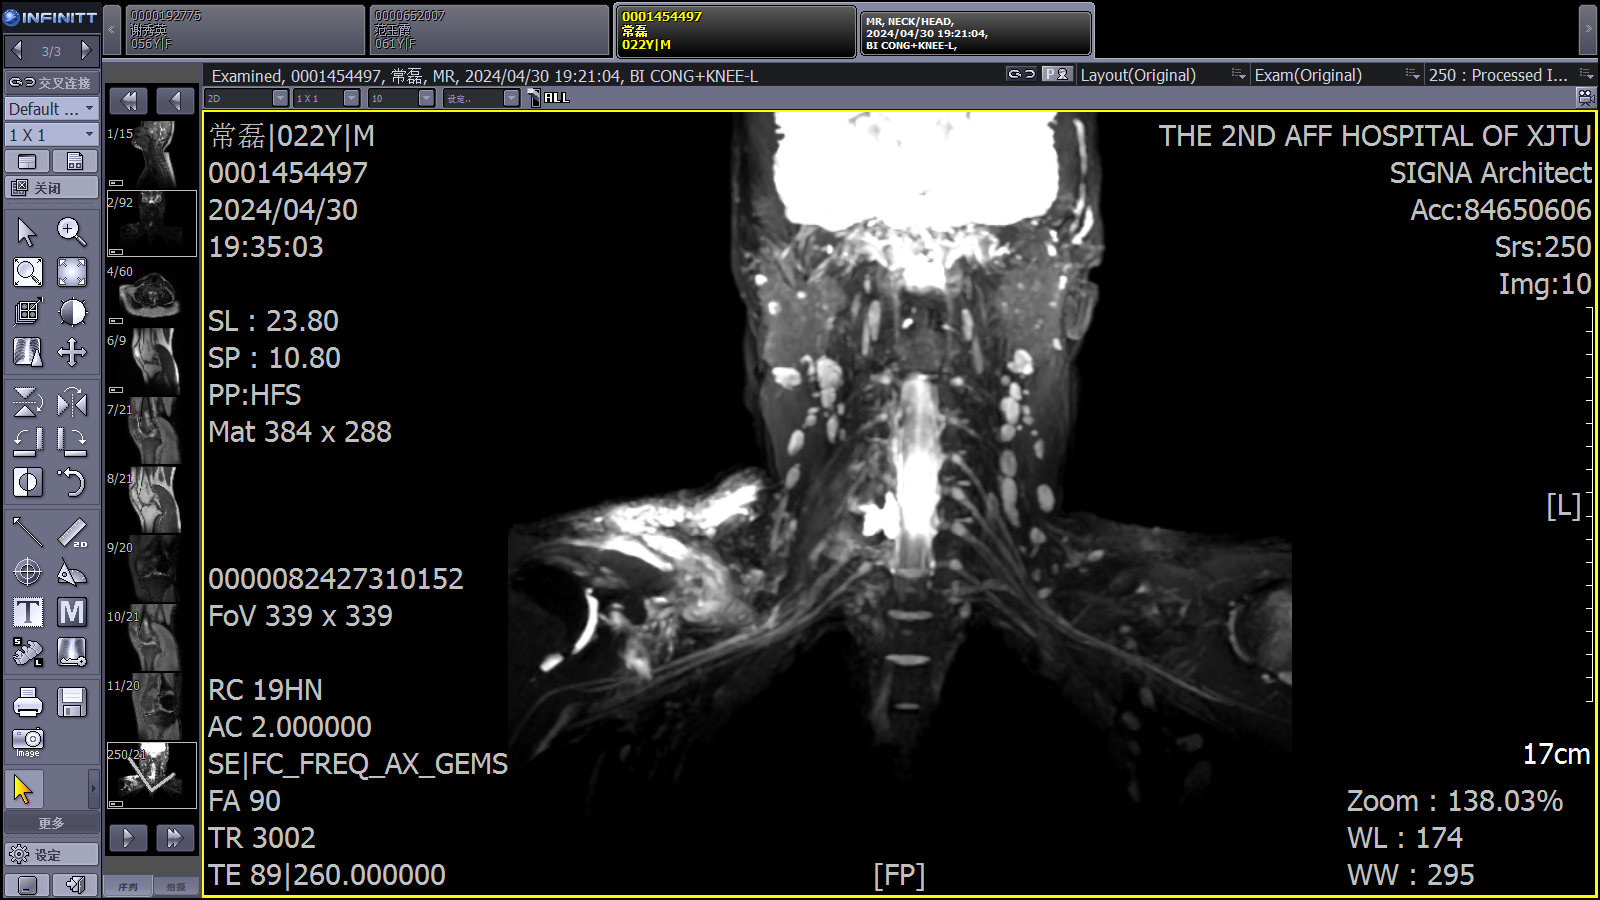

近日,我院骨科中心脊柱与骨肿瘤病区收治一位车祸伤后全臂丛神经损伤的年轻患者,该患者伤后右侧上肢肩、肘、腕关节无自主活动,肌力0级。入院后王栋主任、秦杰副主任医师、李京住院医师以及赵海平和朱琳规培医师对患者进行了详细的检查和评估,在李珂护士长、陈静副护士长和赵辰护士的悉心呵护以及康复医学科张司铎技师的康复指导下,患者右上肢的神经功能得到部分恢复。

臂丛神经作为连接中枢神经与上肢的重要神经通路,一旦受损,将会严重影响患者的日常生活和工作能力。由于臂丛神经损伤的复杂性和治疗难度,许多患者往往面临着治疗周期长、恢复效果不理想等国际难题。为此,脊柱与骨肿瘤病区在我院MDT臂丛神经损伤综合治疗的基础上,积极联系国内知名臂丛损伤专家,为患者提供更加优质、高效的医疗服务。